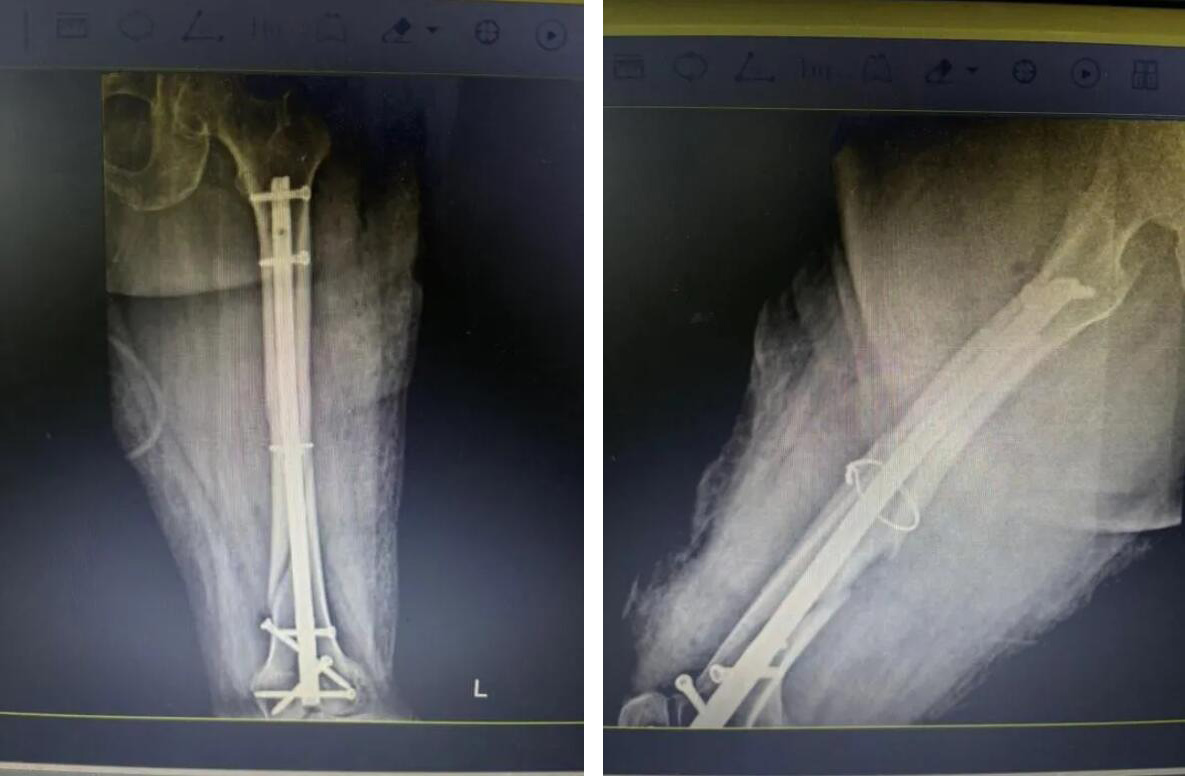

經(jīng)過充分準備,醫(yī)療團隊決定為俞奶奶實施 “閉合復位微創(chuàng)內(nèi)固定術(shù)”。

與傳統(tǒng)開放手術(shù)不同,醫(yī)生不在骨折處做長切口,而是通過幾個僅1-2厘米的“鑰匙孔”小切口,在C型臂X光機的精準導航下,將骨折斷端巧妙地對合復位,然后植入髓內(nèi)釘進行堅固固定。

手術(shù)歷時約一小時,過程非常順利。術(shù)中出血量極少,最大程度減少了對患者生理機能的干擾。